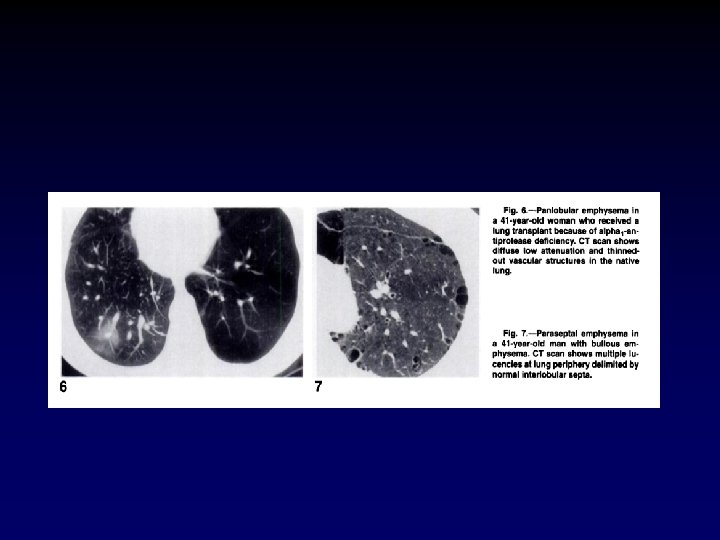

Emhpysema- HRCT Normal Emphysema

Normal Lung Centriacinar Emphysema Panacinar Emphysema

Emphysema- HRCT Centriacinar Emphysema Panacinar Emphysema